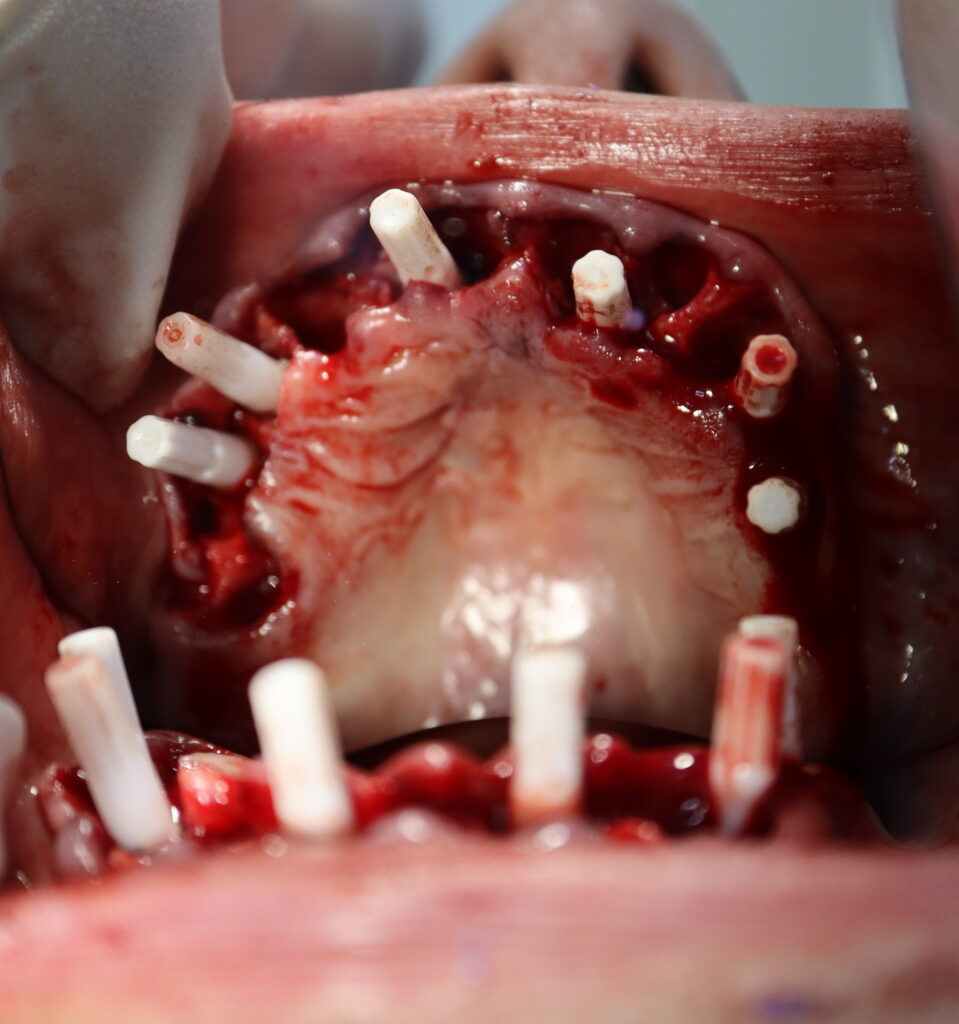

Процесс работы

На верхней челюсти были удалены зубы и проведена комплексная имплантация по системе All-on-6,

установлены 6 имплантатов Megagen AnyOne.

процесс имплантации

Это фото может содержать тяжелый для восприятия контент